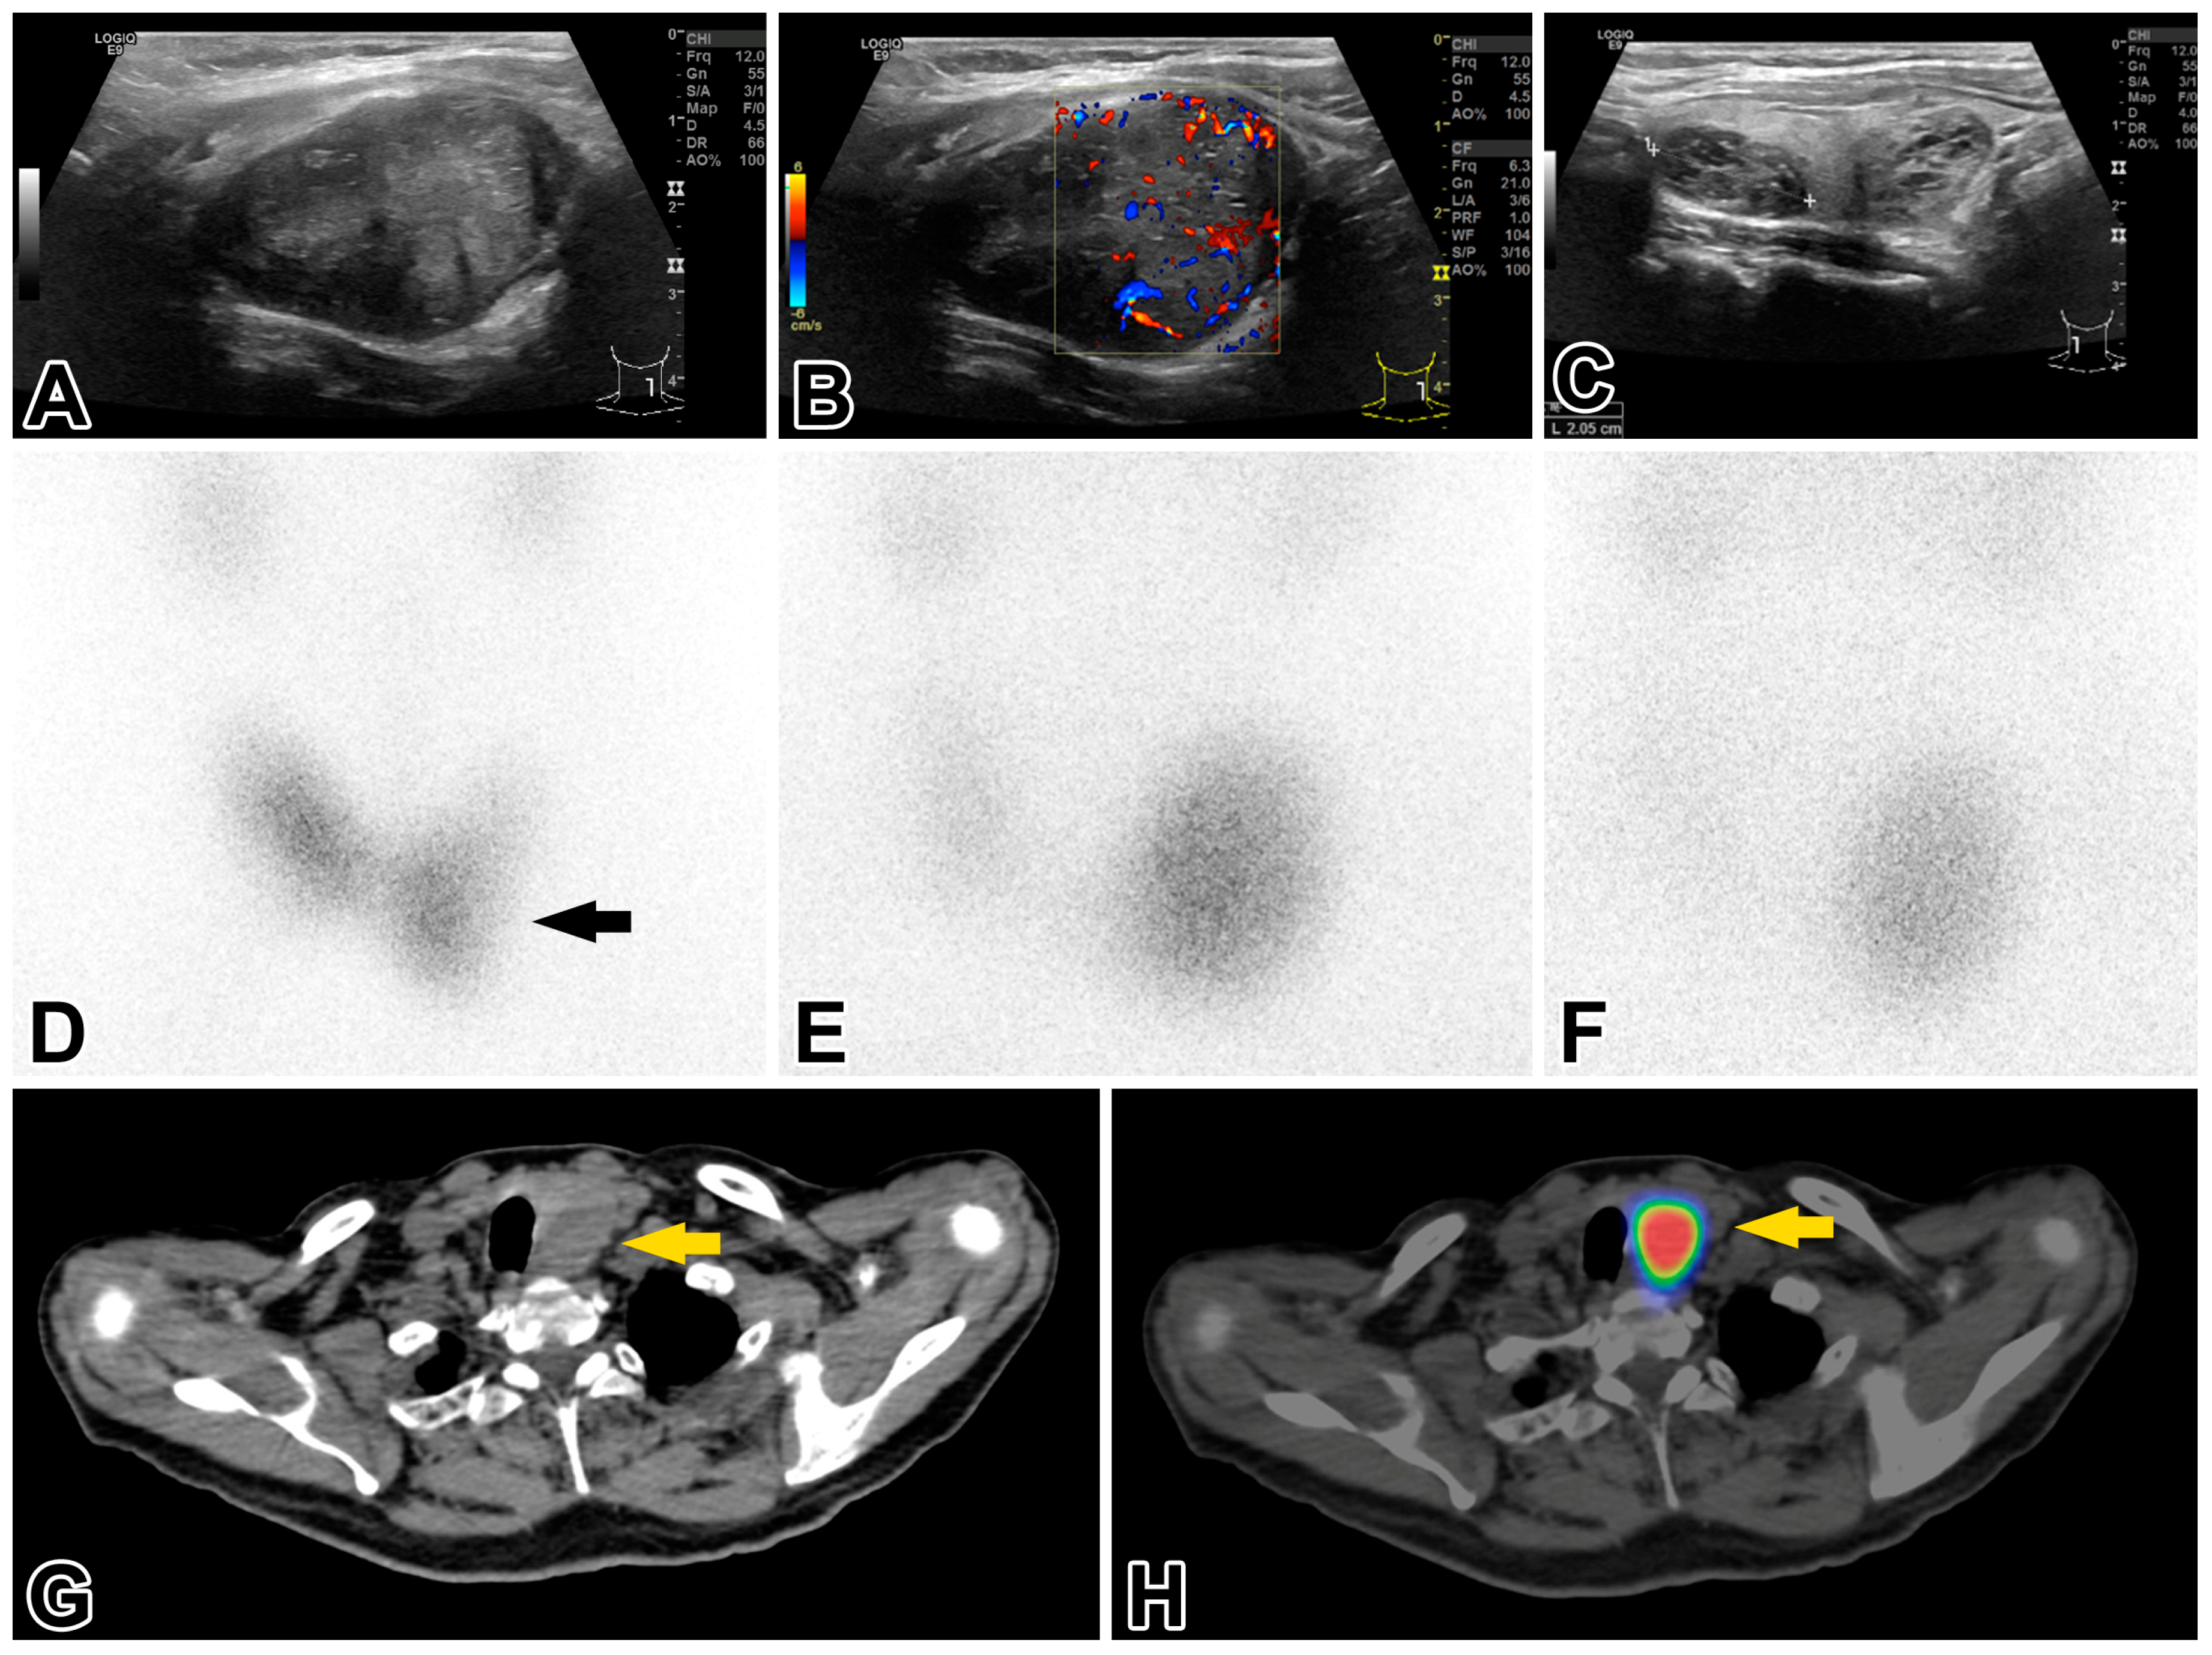

An initial sonographic examination of the neck, chest, and abdominal organs revealed a 41 × 31 × 43 mm EU-TIRADS 3 nodule [13] in the left thyroid lobe and four smaller EU-TIRADS 2 nodules in the right thyroid lobe. Enlarged or abnormally structured cervical lymph nodes were not detected. A fine needle aspiration biopsy (FNAB) was performed on the EU-TIRADS 3 nodule. The cytologic findings did not raise the suspicion of malignancy, and they were compatible with Hashimoto thyroiditis. The blood test for thyroid function found elevated TSH levels (7.95 mIU/L; range 0.27–4.2) and free triiodothyronine and tetraiodothyronine values close to the lower cutoff in the reference range. The level of thyroglobulin, anti-thyroglobulin antibodies, and anti-thyroid peroxidase antibodies were within normal limits. The functional data did not support the diagnosis of Hashimoto thyroiditis. The thyroid region was reexamined by an expert in ultrasonography and nuclear imaging of the thyroid (S.G). The left thyroid lobe, with dimensions 35 × 38 × 48 mm, contained a 30 × 34 × 43 mm solid nodule (Figure 1A–C) that compressed and dislocated the thyroid gland. 99mTc pertechnetate thyroid scintigraphy revealed a thyroid hormone-nonproducing cold nodule in the middle lower third portion of the left thyroid lobe (Figure 1D). This nodule had been examined previously by FNAB. 99mTc-MIBI subtraction parathyroid scintigraphy visualized an area of increased radioactive uptake at the lower third of the left thyroid pole in the 10 and 120 min delayed images (Figure 1E,F). Subsequent single photon emission computed tomography (SPECT/CT) of the neck and skull demonstrated a well-circumscribed, inhomogeneous rounded lesion in the enlarged left thyroid lobe that had dislocated the trachea (Figure 1G,H). Based on these findings, a preoperative diagnosis of a large intrathyroidal parathyroid adenoma and concomitant multinodular thyroid disease was established. A left-sided total and right-sided subtotal thyroidectomy was performed. The postoperative period was eventless.

Figure 1.

Neck ultrasound revealed (A) a large, hypoechoic, slightly irregularly shaped but sharply contoured, heterogeneous, solid nodule in the caudal half of the left thyroid lobe (EU-TIRADS 3); (B) the nodule exhibited enhanced central and peripheral vascularization; and (C) there were several smaller EU-TIRADS 2 nodules in the right lobe, displaying purely spongiform structures. Thyroid scintigraphy (D) showed a contour-deforming activity defect in the middle lower third of the left lobe, corresponding to a cold nodule (arrow). Parathyroid scintigraphy demonstrated a 99mTc-MIBI-enriched nodule in the left lobe corresponding to a large parathyroid neoplasm. (E) The early phase (10 min) and (F) late phase (120 min) parathyroid SPECT/CT. (G) Axial slices of native (low-dose) CT images show an inhomogeneous hypodense lesion of 40 × 32 mm2 axial diameter in the lower half of the left thyroid lobe, not sharply demarcated from it, with a dislocation of the trachea to the right (yellow arrow). (H) The marked lesion displays an intensely enhanced radiopharmaceutical uptake in SPECT/CT fused images.